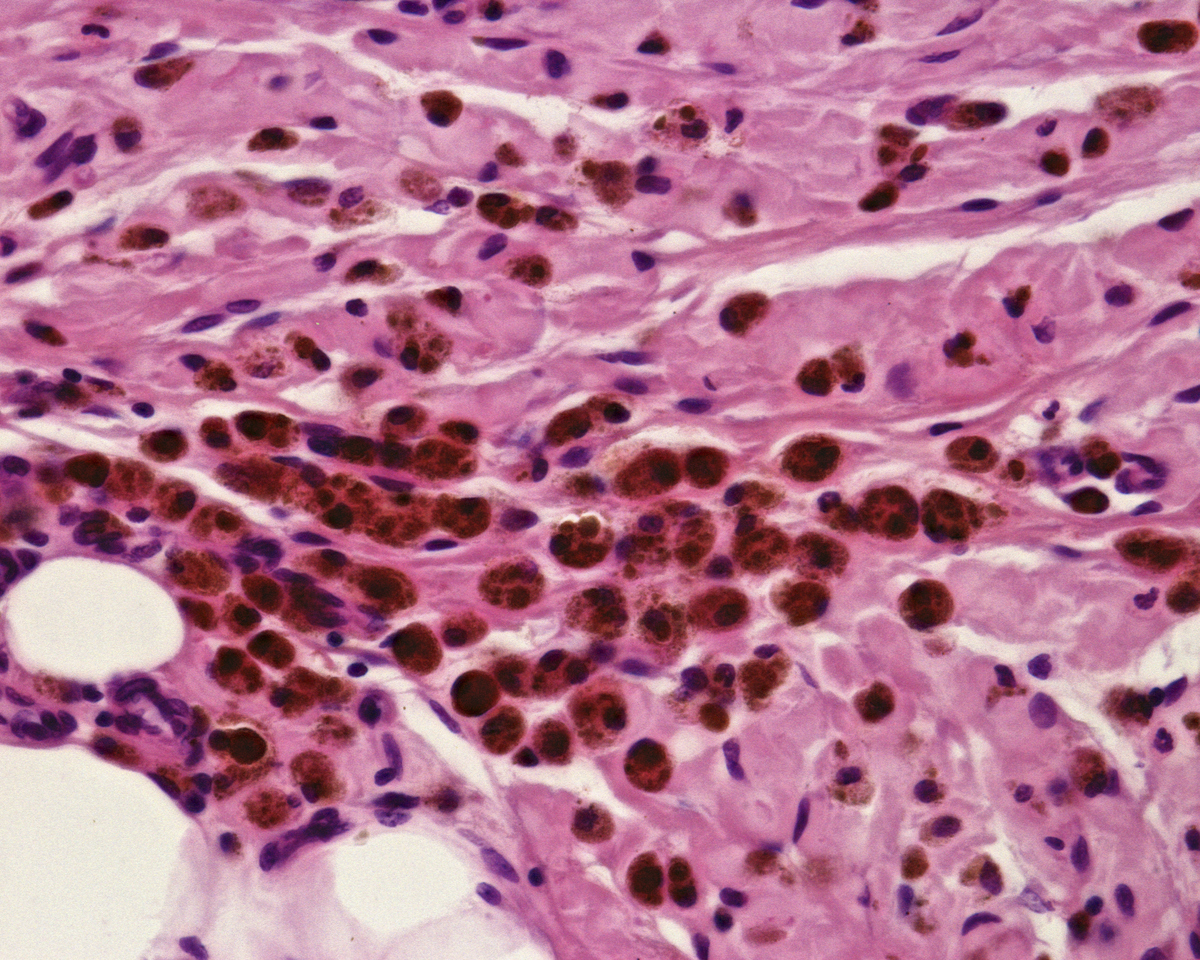

牛(波斯塔鲁斯种,安格斯品种,年龄12-18个月)被放养在一个有围栏的开放草地上,可以自由进食澳大利亚本土草和苜蓿干草。该牧场的密度通常是每10英亩放养一只动物。从屠宰场收集到的正常的母性生殖道组织(每组12个,每组4个)立即用冰冷的Dulbecco改良鹰氏培养基(Sigma,美国)运送到实验室。到达后,组织用含有1%青霉素/链霉素和两性霉素的磷酸盐缓冲液简要清洗,以去除多余的血液并减少初始微生物负荷。子宫被小心地取出,其余的组织(阔韧带、输卵管和卵巢)被丢弃。然后,内膜从肌层中手术分离出来。然后将内膜切成2厘米的块,并放置在Milli-Q水中(含有1%青霉素/链霉素和两性霉素),在室温下磁力搅拌器上不断搅拌过夜。新鲜的Milli-Q水每3到4小时更换一次。每批脱细胞化的子宫内膜组织包含来自四个不同动物的代表性样本。在用Milli-Q水洗涤24小时后,每批内膜组织(n = 4混合)用相应的去细胞化试剂处理:方案1(P1)-4% SDS(Sigma),方案2(P2)-1% SDS,方案3(P3)-4% SDC溶液(Sigma)。每个方案都在常温下(搅拌板)下进行,新鲜溶液每3到4小时更换一次,直到所有组织块变得透明(通常需要4到5天)。经过去细胞化处理后,组织在过夜的水中进行了彻底冲洗,然后在室温下用1M NaCl中的2,000 kU DNase(Sigma)处理3小时。然后,脱细胞化的组织在Milli-Q水中再洗涤2天,多次更换水,以消除任何SDS / SDC的细胞毒性残留物,然后进行冷冻干燥和研磨成粉末。